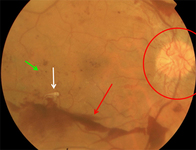

Proliferative diabetic retinopathy: new vessels elsewhere (white arrow), vitreous (intra-gel) haemorrhage (green arrow), retrohyaloid haemorrhage (red arrow)

Courtesy of Moorfields Photographic Archive; used with permission